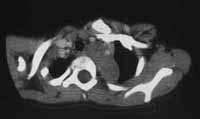

Рис. 5. Нефробластома справа у больной П., 6 лет.

А-Б, С-Д – опухолевый тромб (дефект контрастирования) в просвете НПВ, контрастное вещество визуализируется в просвете сосуда тонкой пристеночной полоской (А).